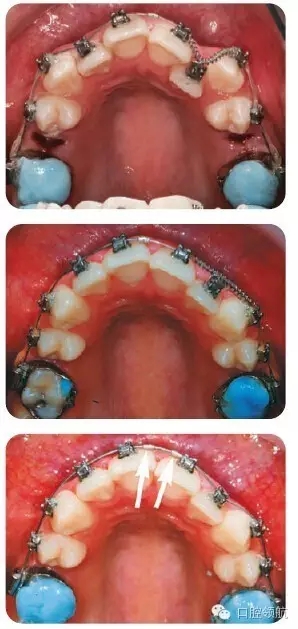

圖3.2中治療措施的說明

拔除上頜雙側(cè)第二前磨牙后,粘結(jié)上頜托槽,使用0.013英寸鎳鈦圓絲,配合UL1、UL3間的鎳鈦推簧,為UL2的納入提供間隙。同時(shí),以上頜第一磨牙為支抗,采用彈性鏈狀結(jié)扎圈拉尖牙向遠(yuǎn)中移動(dòng)。UL2通過結(jié)扎絲懸吊至弓絲上,以促進(jìn)其唇向移動(dòng)。由于可能導(dǎo)致的牙弓變形,牙齒傾斜移動(dòng)以及難以預(yù)估的反作用力,我們通常并不推薦在鎳鈦圓絲上使用主動(dòng)力。但是,有研究指出自鎖托槽穩(wěn)定的鎖結(jié)效果可以有效地規(guī)避上述風(fēng)險(xiǎn)。

圖3.2(第三幅圖)中所示的箭頭是什么?

這是在弓絲上放置的小型金屬停止扣,用以阻止治療初期出現(xiàn)的弓絲滑脫。否則,由于自鎖托槽與弓絲間的滑動(dòng)摩擦力過小,弓絲可能由一側(cè)滑脫,甚至刺入磨牙后墊造成損傷。

為什么在上頜第一磨牙面放置玻璃離子墊高材料?

這項(xiàng)措施能夠使上下頜脫離咬合接觸,從而有利于糾正UL2鎖。也可以使用活動(dòng)矯治器或固定的咬合打開裝置達(dá)到此目的。